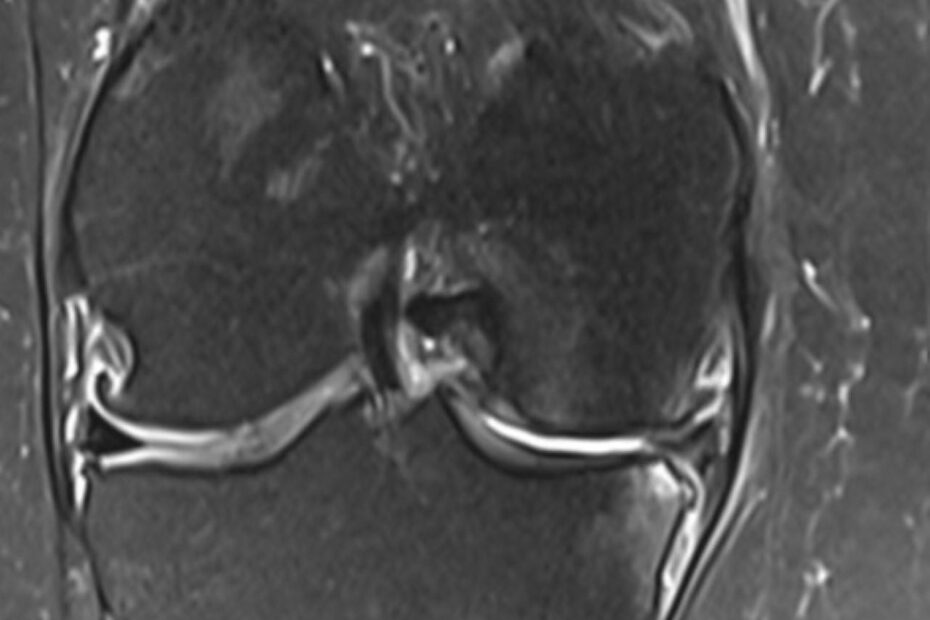

Eine MRT Knie ist eine der häufigsten durchgeführten MRT-Untersuchungen. Schmerzen im Knie können viele Gründe haben, da das Knie aus einem Gelenkkomplex besteht. Diesen Gelenkkomplex kann man in einer Knie MRT detailliert darstellen, um präzise Diagnosen zu erzielen. Das Knie kann Verletzungen insbesondere beim Sport, aber auch im Alltag erleiden. Laut einer Studie des Robert- … MRT Knie weiterlesen